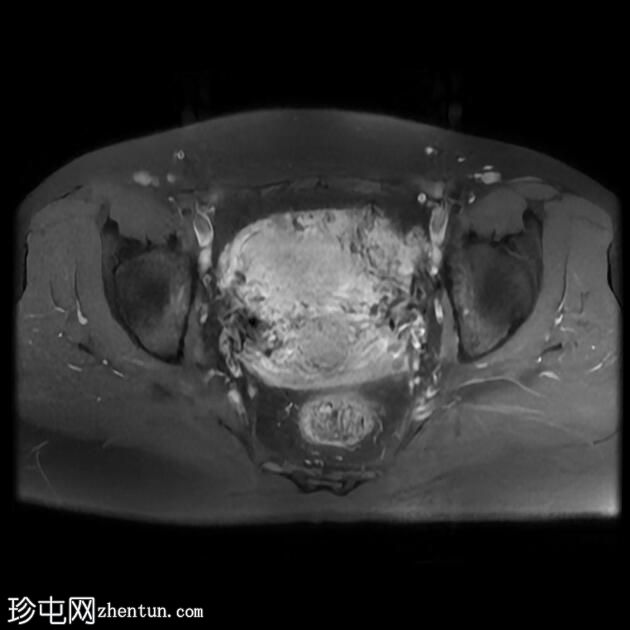

轴位

T1加权像

盆腔MRI显示双侧子宫旁多条迂曲静脉,自子宫肌层延伸至盆腔。

此外,左侧附件可见两个充满液体的单纯性囊肿,大小分别约为31 mm和32 mm;右侧附件可见一个卵泡囊肿,大小约为19 mm。

影像学特征符合盆腔充血综合征的诊断,患者为35岁女性,有慢性盆腔疼痛和痛经病史。